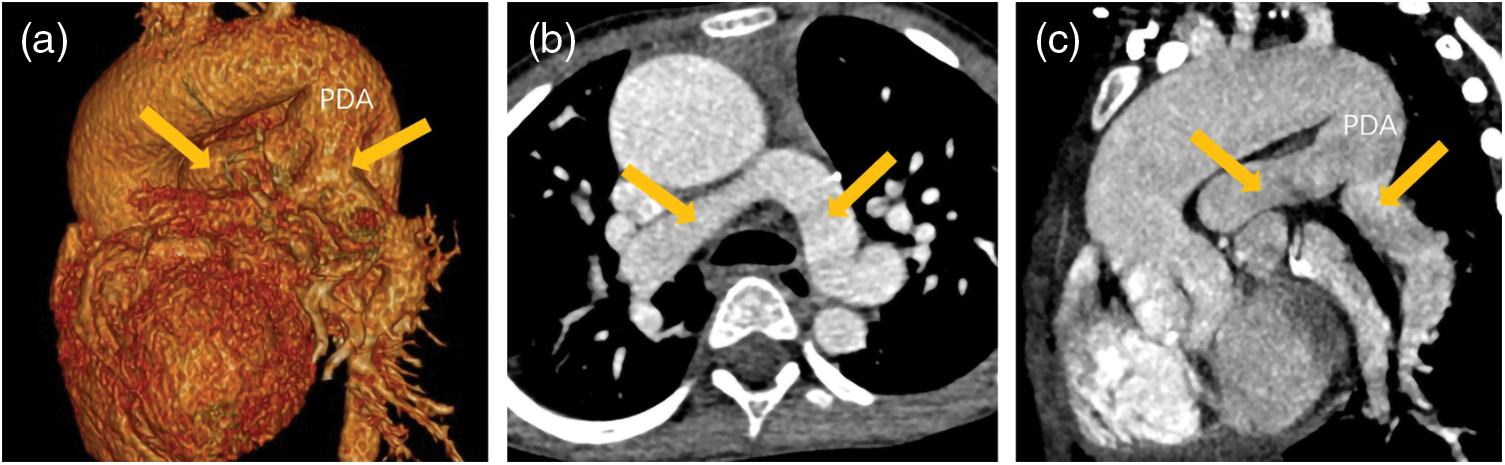

Figure 3: A patient with PA/VSD. The blood supply of his lungs came from patent ductus arteriosus (PDA). His ascending aorta and aortic arch dilated obviously. His PDA was tube-shaped and his left/right pulmonary artery (yellow arrows) developed well. (a) The VR image of PDA and left/right pulmonary. (b) The transverse image of left/right pulmonary. (c) The reconstruction image of PDA and left/right pulmonary